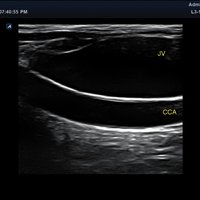

Anwendungsbereiche Abdomen MSK, Nerven, Karotis, periphere Gefäße, Schilddrüse, Mamma

Bildgebungs-Modi B-Modus, CF, M, PW, PD B-Modus, CF, M, PW, PD

• B-Modus: Darstellung zweidimensionale Bilder anatomischer Strukturen